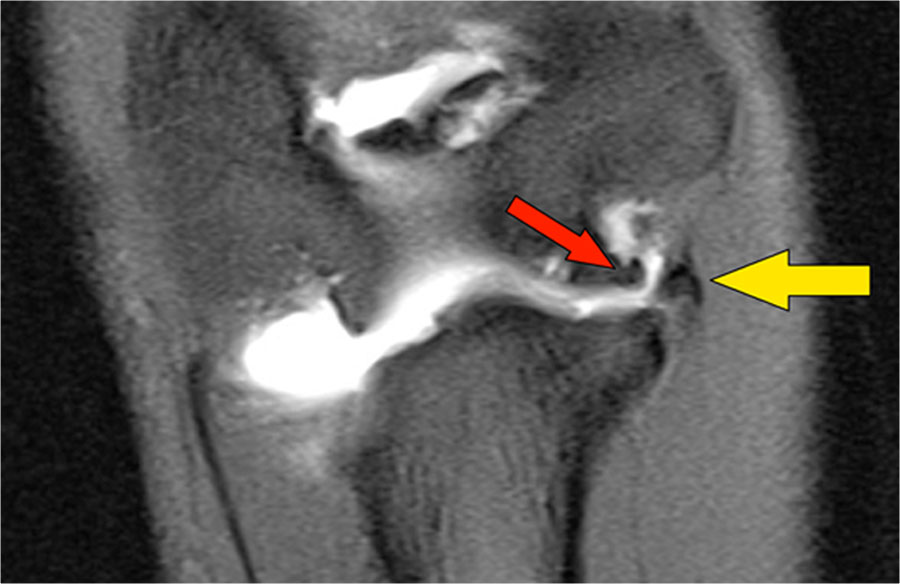

Trên các hình ảnh mặt phẳng coronal, bó trước của dây chằng UCL hiện rõ đẹp, nhưng lưu ý rằng có sự hình thành gai xương ở phần trong của khớp (mũi tên đỏ).

Khi chúng ta đi xa hơn về phía sau có một vùng nhỏ có tín hiệu thấp (mũi tên vàng), đây là một chỗ bong gân của một phần dây chằng bên trụ (UCL).

Điều này được thể hiện rõ hơn trên phim X-quang.

Continue with the axial scan.

Khi quan sát trên lát cắt ngang (axial), chúng ta có thể nhận thấy sự hình thành gai xương khổng lồ.

Lưu ý rằng dây thần kinh trụ (mũi tên màu xanh) nằm cạnh các gai xương này và những bệnh nhân này có thể biểu hiện bệnh lý thần kinh trụ.